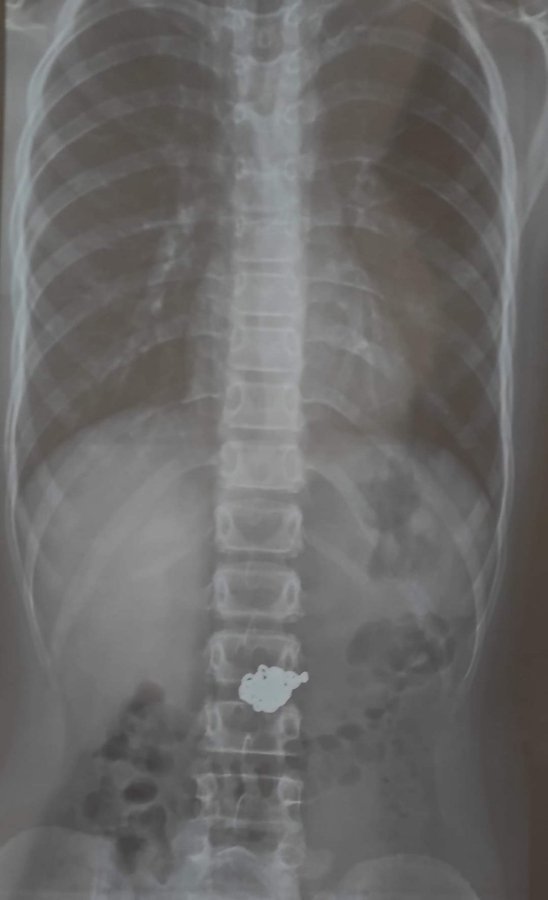

17 липня до Вінницької обласної дитячої клінічної лікарні надійшли чотири звернення через сторонні тіла у шлунково-кишковому тракті дітей віком від 3 до 10 років.

«Лікар-ендоскопіст дитячої обласної лікарні Артур Москаль зазначив, що всі випадки сталися після 23:00, коли діти проковтнули сторонні предмети. Особливу небезпеку становлять магніти, батарейки, монети та дрібні прикраси», - йдеться у повідомленні.